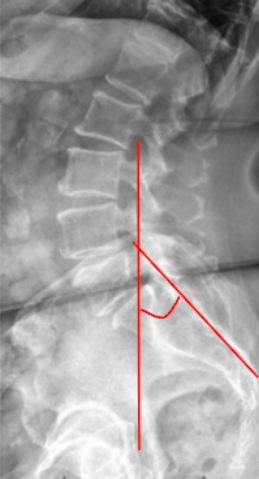

1) Description of Measurement

Boxall’s Angle, also known as the Sacral Inclination Angle, is a radiographic parameter used to assess sacral orientation relative to the vertical axis of the body. It quantifies the anterior tilt of the sacrum, serving as an indirect measure of lumbosacral alignment and pelvic posture.

This measurement is especially useful in evaluating spondylolisthesis, sagittal imbalance, and pelvic compensation. An increased Boxall’s Angle indicates a more anteriorly inclined sacrum and, consequently, greater lumbar lordosis and shear stress across the lumbosacral junction. A reduced angle corresponds to posterior pelvic rotation, often seen in flat-back or compensatory alignment patterns.

2) Instructions to Measure

• Obtain a standing lateral lumbosacral X-ray including the full sacrum and lumbar spine.

• Identify the posterior surface of the sacrum—a straight line can be drawn along its posterior cortical margin.

• Draw a vertical reference line perpendicular to the horizontal (ground) plane.

• Measure the angle formed between the posterior sacral line and the vertical reference line.

• This is the Boxall’s Angle (Sacral Inclination).

• The angle opens anteriorly, representing the degree of sacral tilt relative to the vertical axis.

• Record the result in degrees (°).

• For consistency, ensure that the patient’s posture is neutral (knees extended, pelvis level) during X-ray acquisition.